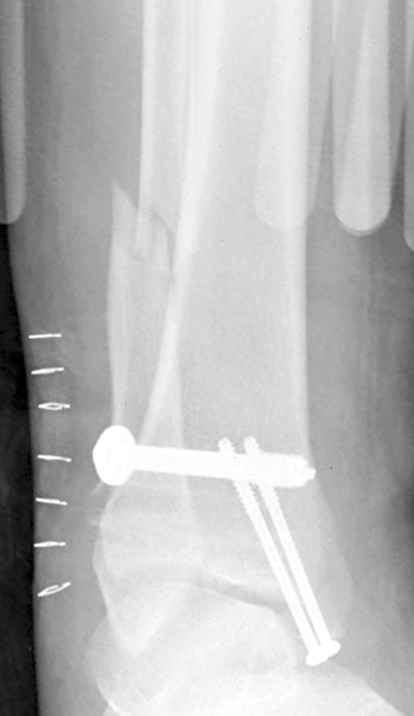

Если до сих ничего не сделано, с артродезом сустава в данный момент я бы повременил, на выставленных январских снимках хорошо сохранившийся сустав, а в "мортиз" (трехчетвертной) и на боковых снимках не менее 5 мм укорочение малоберцовой кости. Косые переломы лучше фиксировать пластинами, как то мы разбирали случай, где было отмечено, что это закон "таранная кость всегда следует за малоберцовой".

В данном случаи я бы уговорил больного на реконструкцию, для этого после удаления шурупов, спереди очистить от рубцов синдесмоз, несросшуюся наружную лодыжку - остеотомия по линии перелома и компрессирующий (lagging technique) кортикальный шуруп 3.5 мм по поперечнику остеотомии. Следующий этап - восстановление длины малоберцовой за счет удлинения, сделать поперечную остеотомию где-то на уровне сантиметр выше вашего синдесмозного шурупа, наложить длинную пластинку, прикрепить пластину за дистальный конец двумя или тремя шурупами; сохраняя контакт пластины с костью, имеющимся

compression&tension device AO system (при отсутствии любой lamina spreader подойдет, создать дистанцию между пластиной и шурупом, проведенным проксимальнее пластины) толкая проксимальный отдел пластины, низвести пластину, мортиз рентгенограмма подскажет на сколько. Если заранее сделать предоперационный план (ренгенограмма другой стороны), тогда точно можно определить, на сколько вам необходимо сделать поперечную остеотомию малоберцовой кости, для закрытия создавшегося дефекта.

Убедившись, что желаемая длина восстановлена, окончательная фиксация пластины, при этом через пластину пару 3.5 мм шурупов на синдесмоз, предпочтительно в четыре кортекса и оставить на 3 мм длиннее, если под нагрузкой синдесмотический шуруп сломается, сломанный конец легче удалить с медиальной стороны.

Медиальная сторона не в нагрузочной зоне, и там большая дыра - если есть 2.7 мм шурупы, или пару спиц в ваших условиях или методика Лазарева. Необходимо уделить внимание к мягким тканям, обнажается кость с латеральной стороны и у места где проводится остеотомия.

После 5-6 недели после травмы сделана повторная операция, обошлись без удлинения малоберцовой.